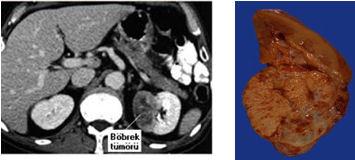

Bilgisayarlı Tomografi (CT): Doku dansitesi (yoğunluğu) ölçülerek tümörün, benign ya da malign olup olmadığı %90 doğrulukta belirlenir. Aynı zamanda lokal yayılım, regional lenfadenopati ve renal ven ya da vena cavada tümör trombüsü, karaciğer, dalak metastasları tanısı CT ile mümkün olmaktadır.

Patolojisinde; yuvarlak-oval, kirli sarı renkte yer yer hemorajik, nekrotik, kistik ve kalsifik alanları yer yer yumuşak ve sert alanlar içeren pseudokapsüllü bir tümördür.

Başlangıçta intrarenal olan tümör ekspansif (çevre dokuya doğru genişleyerek) olarak gelişir, tümör çevresindeki böbrek dokusunu iterek böbrek konturunu (dış yapısını) bozar. Aynı şekilde kaliksleri ve pelvisi iterek pelvikalisiyel deformasyona (bozulmaya) neden olur. Zamanla böbrek fibroz kapsülünü geçerek perirenal yağ dokuya, Gerota fasyasına, çevre doku ve organlara ulaşır, böbrek fikse (sabit, hareket etmeyen) kitle halini alır.